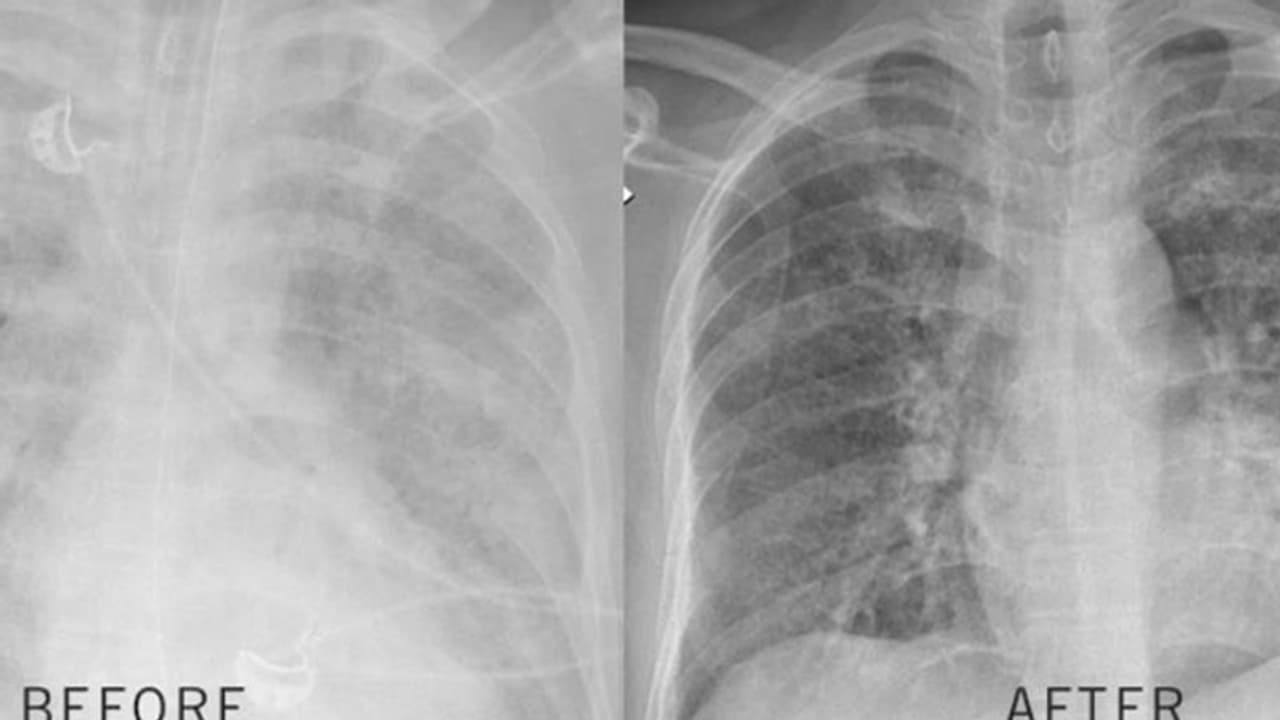

അപൂർവ രോഗം ബാധിച്ച് ഏറെ നാളായി ശ്വസിക്കാൻ ബുദ്ധിമുട്ടിയ ബംഗ്ലദേശിയുടെ ശ്വാസകോശം കഴുകി വൃത്തിയാക്കി അബുദാബിയിലെ ക്ലിവ് ലാൻഡ് ക്ലിനിക്. ശ്വാസകോശത്തില് പ്രോട്ടീന് അടിഞ്ഞു കൂടി മാരകമാകുന്ന പള്മൊനറി ആല്വിയോളാര് പ്രൊട്ടീനോസീസ് എന്ന അപൂര്വ്വ രോഗമായിരുന്നു ഡ്രൈവറായ ബംഗ്ലാദേശ് സ്വദേശിക്കെന്ന് ഡോ. റേധ സോയുലമാസ് പറഞ്ഞു.

ഡോ. റേധിന്റെ നേതൃത്വത്തിലുള്ള സംഘമാണ് ശസ്ത്രക്രിയ നടത്തിയത്. നാല് മണിക്കൂർ നടന്ന ശസ്ത്രക്രിയയിലാണ് ശ്വാസകോശം കഴുകി വൃത്തിയാക്കിയത്. ശ്വാസകോശം കഴുകി വൃത്തിയാക്കുമ്പോഴും വിവിധ അവയവങ്ങളിലേക്കുള്ള രക്തയോട്ടം തുടരാന് കൃത്രിമ ശ്വാസകോശം ഘടിപ്പിച്ചായിരുന്നു ചികിത്സ. 26 ലിറ്റര് വെള്ളം കഴുകാന് ഉപയോഗിച്ചു.